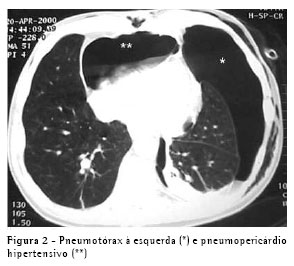

O problema foi resolvido, e os cateteres foram removidos. No dia seguinte, o paciente apresentou hipotensão, taquicardia e dispnéia. Por motives técnicos, não foi possível realizar um ecocardiograma. A TC mostrou um pneumotórax anterior esquerdo e um pneumopericárdio grande (Figura 2). Um tubo torácico 32 Fr foi inserido na cavidade pleural esquerda, e o problema foi totalmente resolvido. O paciente também foi submetido a uma pleurodese com talco em suspensão. A mesma solução simples (drenagem pleural) foi usada neste segundo caso.